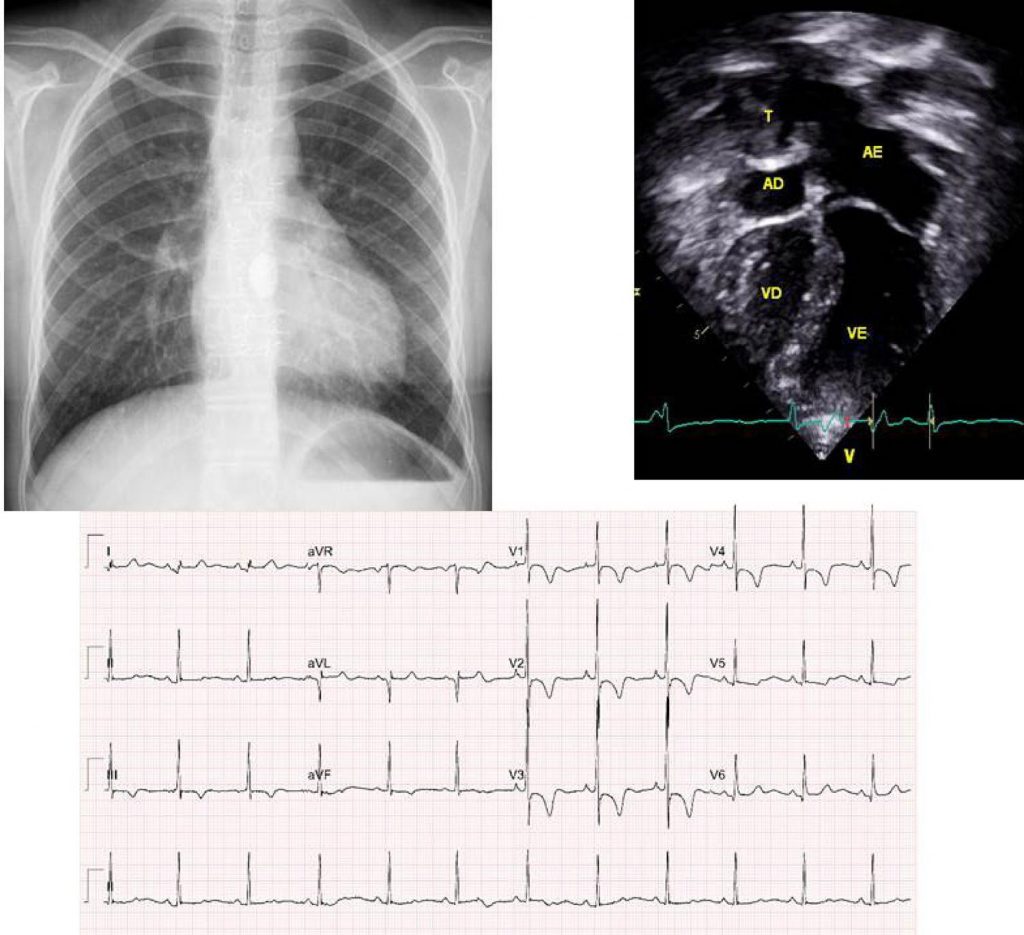

Jovem de 17 Anos com Atresia Pulmonar e Septo Ventricular Íntegro, Submetido à Operação de Fontan e com Persistência da Fístula Coronário-Cavitária

Atresia pulmonar com septo ventricular íntegro constitui-se em anomalia congênita com interrupção total do fluxo de sangue entre o ventrículo direito e o tronco pulmonar, e em geral não é acompanhada de defeitos associados, exceto pela comunicação interatrial, presente em 20%, com predomínio do forame oval patente. Decorre a atresia valvar da falta de desenvolvimento embriológico dessa estrutura fibrosa, podendo se localizar a nível valvar (membrana fibrosa), mas também a nível infundibular (fundo cego). Como consequências, surgem hipertrofia miocárdica e hipoplasia de ventrículo direito, hipoplasia do anel e da valva tricúspide, insuficiência tricúspide discreta e fluxo pulmonar dependente do canal arterial. Em vista da maior hipertensão em ventrículo direito, formam-se através de sinusóides conexões diretas com a circulação coronária, com fluxo em direção à aorta. Diz-se nessa situação que a circulação coronária é dependente do ventrículo direito e, quando se apresenta em grande magnitude, predispõe ao infarto do miocárdio, a arritmias, e também a sobrecarga volumétrica ventricular direita, por fluxo retrógrado da aorta.

Em casos nos quais a atresia valvar se desenvolve mais tardiamente no feto, a cavidade de ventrículo direito pode estar bem formada com suas três porções, de via de entrada, a trabecular e a da via de saída e, como consequência, ocorre insuficiência tricúspide acentuada, até com alteração tipo Ebstein da valva redundante e mixomatosa, adelgaçamento da parede ventricular, disfunção ventricular e insuficiência cardíaca direita, esta sobreposta à hipóxia. Em geral, não acompanha outros defeitos associados, e as artérias pulmonares se mostram de tamanho adequado. Nesses casos, não há a formação de conexão do ventrículo direito com as artérias coronárias por sinusóides.